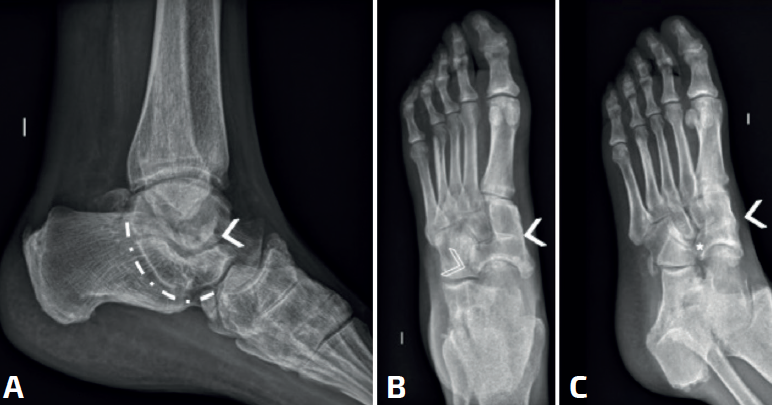

El hocico del oso hormiguero es diagnóstico de una coalición CN. Inicialmente descrito en las radiografías oblicuas, también puede ser visible en las proyecciones laterales(37,42,43)(Figura 6A). El proceso anterior del calcáneo normalmente es triangular, pero se alarga en las coaliciones y la punta es cuadrada como el hocico de un oso hormiguero. Un estudio de Crim y Kjeldsberg(22) demostró en radiografías laterales una sensibilidad del 72% y una especificidad del 90% del signo del oso hormiguero, y del 90-100% de los casos en las oblicuas(40,41). Será incompleta en caso de fibrocartilaginosa y completa en las uniones óseas.

El hocico del oso hormiguero inverso: en la radiografía AP en carga del pie, se verá el proceso lateral del escafoides más alargado (Figura 6F, flecha). Normalmente los márgenes están alineados con la cabeza. En las coaliciones, el borde lateral tiende a estar más alargado (Figura 6B, asterisco), en algunos casos su borde es cuadrado y parece articular con el calcáneo. La sensibilidad original reportada de este signo fue del 50% y la especificidad fue del 100%(22), aunque un informe posterior encontró una sensibilidad de tan solo el 18%(44).

El pico del astrágalo (talar beak) se produce secundariamente por la rigidez del retropié(45). La articulación de Chopart aumenta su movilidad a dorsal, el escafoides sube por encima de la cabeza del astrágalo creando con la tracción capsular un pico (es más común en las TC que en las CN) (Figura 7).

El signo de la C o C-sign es el signo directo más fácil de identificar en la vista lateral. Analizando la faceta medial de la articulación subastragalina en las coaliciones TC, que son las más frecuentes (Figuras 7 y 8). Si es distrófico o la línea articular es irregular, sugiere osteoartritis. Los pacientes suelen ser jóvenes al diagnóstico. Posteriormente, en caso de sinostosis con continuidad entre el calcáneo y el astrágalo, un bloque óseo une la voluminosa faceta medial distrófica al sustentaculum tali. Tiene la forma de un arco convexo posteriormente: de ahí el “signo de la C”(45). En pies planos puede ser positivo sin coalición(46) (sensibilidad del 88% y especificidad del 87%)(22).

La ausencia de la faceta medial (subastragalina) precisa de una proyección exacta lateral centrada en el retropié(22). Si la articulación subastragalina posterior es visible y bien alineada, la anterior debiera ser igualmente visible; si no, es posible una coalición(22,47) (sensibilidad del 72-100% y especificidad del 42-94%) (Figura 8A).